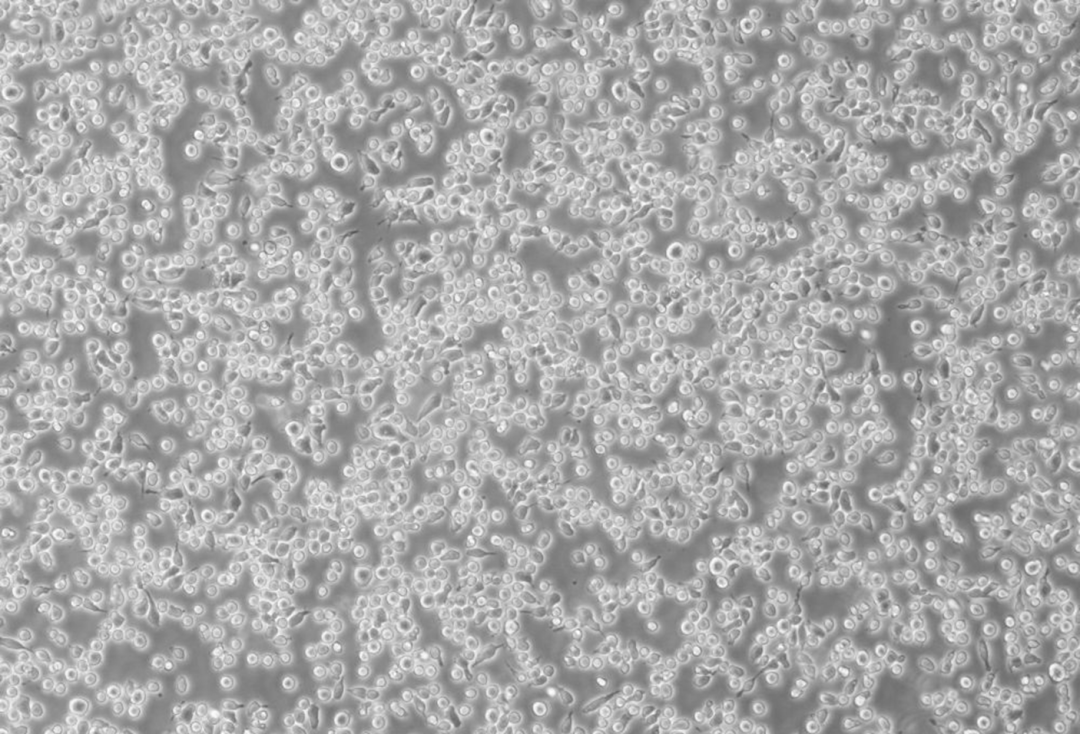

细胞名称: MM.1S(人多发性骨髓瘤细胞)

生长特性: 半贴壁

细胞简介: MM.1S细胞源于患有多发性骨髓瘤的黑人女性患者,CD25+, CD38+, CD52+, CD59+,表达糖皮质激素受体(GR),分泌IgGλ轻链,对地塞米松敏感。

▲细胞正常生长形态照片